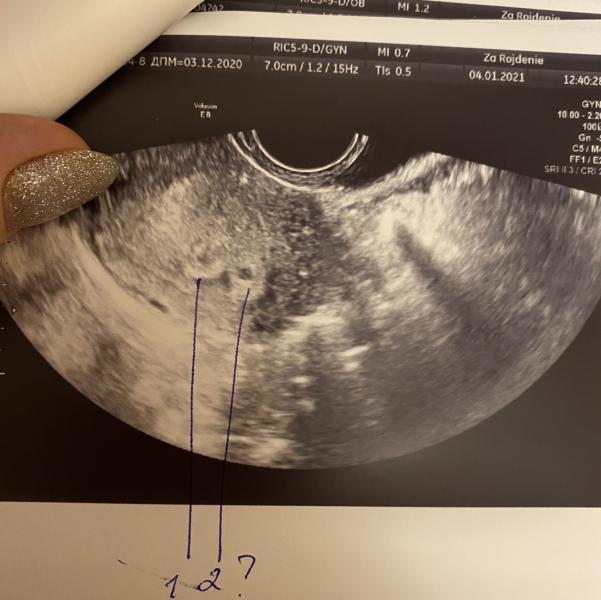

На УЗИ 1пя точно, второе ставят под вопросом. Если это не второе пя, то что же ещё может быть?

Ваши предположения... 1, 2 ?

Если 1, то что это рядом с ним ? 🤔

Читаю вас не первый раз. У меня при нынешней беременности было два плодных яйца, и мелкая миома. Плрдные были один в один, миома же отличается и сейчас и она была дальше от плодных. Узи делала в 6 недель если не ошибаюсь. Думаю у вас двойня))

Я вижу два)